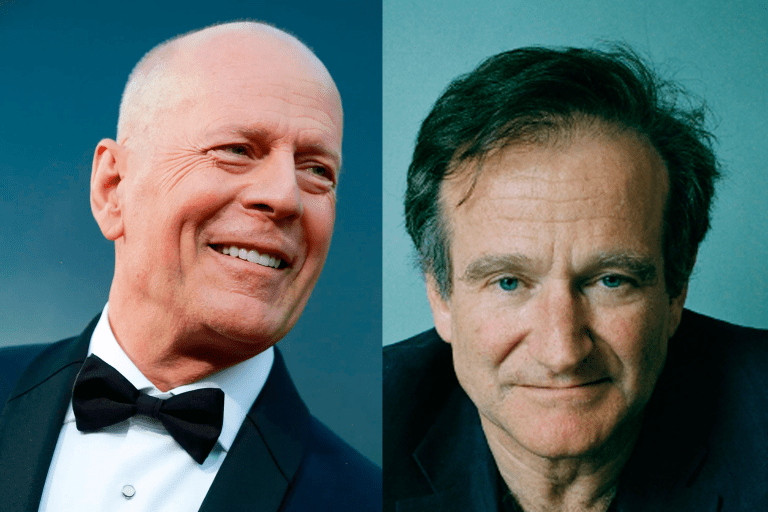

Ambos os atores desenvolveram tipos bastante comuns de demência, mas o que os casos têm em comum?...